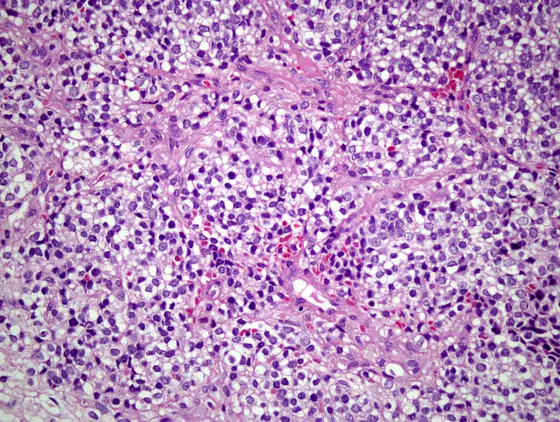

Ewing-Sarkom-Zellen sind klein, rund und undifferenziert. Sie lassen sich ohne molekulare Analysen nur schwer von anderen Tumorzellen abgrenzen, was die Diagnosestellung oft erschwert und verzögert.